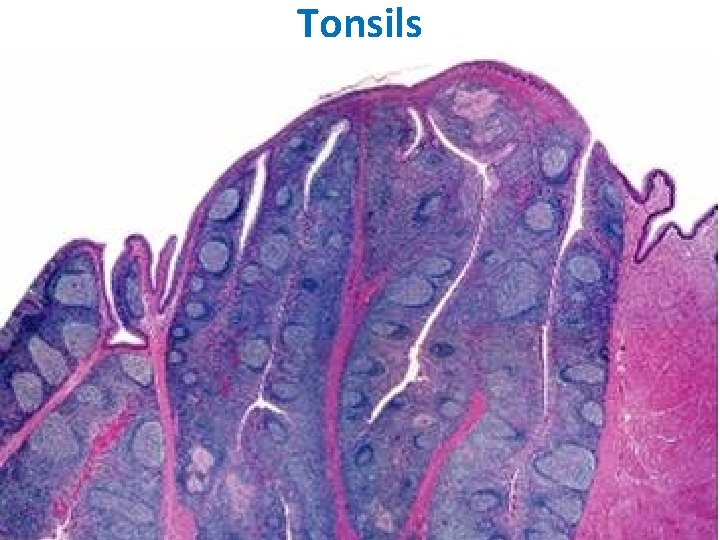

TONSILS These incompletely encapsulated lymphoid aggregates contain many lymphoid nodules; they underlie the mucous membranes (epithelial lining) of the mouth and pharynx. Together with the diffuse subepithelial lymphoid tissue that connects them to form a ring, they guard the common entrance to the digestive and respiratory tracts. The 3 types, palatine tonsils, the pharyngeal tonsil, and lingual tonsils, differ in number, epithelial covering, presence (or absence) and number of epithelial invaginations or crypts, and presence (or absence) of a definitive partial capsule. Most specific structures: epithelial linings, lymphatic nodules under the epithelium with lymphatic infiltration and crypts.

Tonsils